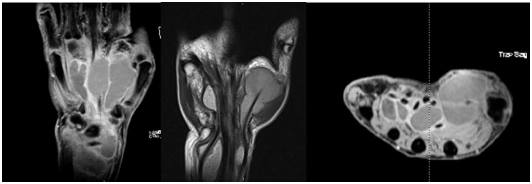

Simple X-rays revealed no abnormal findings in bone, joint, and soft tissue. Magnetic resonance imaging (MRI) (Figure 1) was suggestive of flexor tendon sheath tenosynovitis. It revealed a fluid collection in the tendons sheath of the first to fourth fingers and in the flexor compartment along the ulnar and radial side of the wrist.

Figure 1 fluid collection in the tendons sheath of the first to fourth fingers and in the flexor compartment of the wrist.